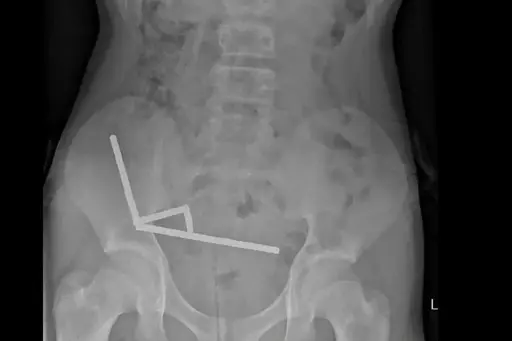

An X-ray showed the magnets had clumped together in four straight lines inside the child’s intestines.

“These appeared to be in separate parts of bowel adhered together due to magnetic forces,” they said.

I kinda get it. These things come as a cylinder. He didn’t so much swallow 100 individual magnets, but rather swallowed a complete cylinder package of them. The x-ray tends to confirm that.

Still, if you’re 13 years old, you’re old enough to understand why you shouldn’t swallow everything in front of you.